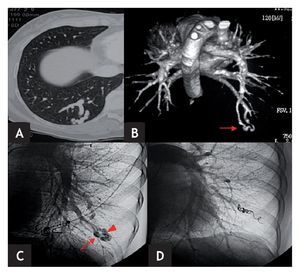

Figura 1. A y B) Paciente n.º 4. A) TC torácica con contraste: malformación arteriovenosa pulmonar (MAVP) en LID. B) Reconstrucción"volume rendering" en visión posterior en la que se observa mejor la MAVP en LID. C y D) Paciente n.º 2. C) Angiografía selectiva pulmonar izquierda donde se aprecia una MAVP simple en LII con una única rama aferente (flecha) y una única vena de drenaje (cabeza de flecha). D) Angiografía selectiva pulmonar izquierda postembolización concoils. Exclusión de la MAVP.